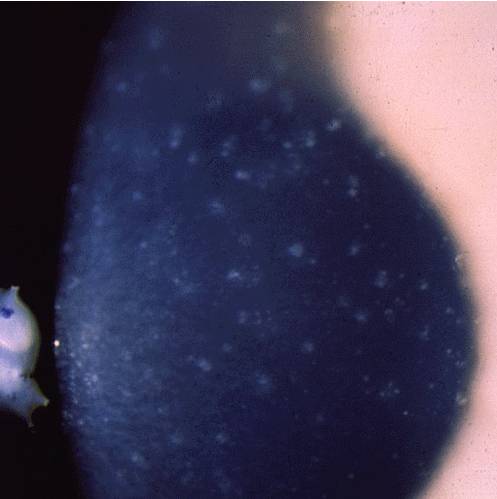

Имеет аутосомно-доминантный тип наследования (ген TGFBI, локус 5q31), билатеральная, симметричная. Заболевание проявляется в первую декаду жизни. Осмотр за щелевой лампой выявляет хорошо видимые гранулы, которые кажутся белыми при прямом освещении. При ретроиллюминации эти гранулы состоят из чрезвычайно мелких, полупрозрачных точек, выглядят как вакуоли, стеклянные осколки или измельченные крошки. Помутнения не захватывают лимбальную зону. У детей коричневые гранулы, образующие вихревидный рисунок, расположены относительно поверхностно и распространяются к слою Боумена. В дальнейшем гранулы простираются в глубокие слои стромы вплоть до десцеметовой мембраны. Блики и светобоязнь являются относительно ранними симптомами. Так как на начальных этапах регулярность передней поверхности не нарушена, острота зрения остается высокой. С возрастом помутнения прогрессируют, сливаются между собой, острота зрения постепенно снижается. Иногда имеют место рецидивирующие эрозии. В развитых стадиях острота зрения редко снижается менее 0,1. Как правило, к 50-60 годам необходима кератопластика, после которой вероятны рецидивы в течение нескольких лет (от 1 года до 20 лет).